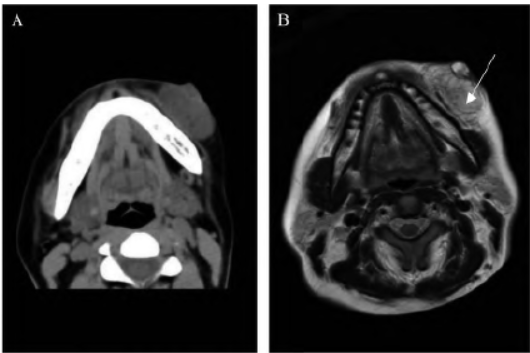

术前颌面部CT 平扫示:左侧颌面部皮下可见团块状软组织密度影,边界尚清晰,邻近皮肤脂肪层浸润(图2A)。颌面部增强磁共振成像

(magnetic resonance image,MRI)示:左侧颌面部皮下异常强化灶,考虑血供占位性病变,低度恶性病变待排除(图2B)。

图2 术前影像学检查。A. 颌面部平扫CT 图像;B. 颌面部增强MRI 图像,箭头示病变处。